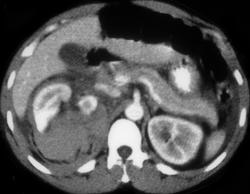

Renal Laceration With Contrast Extravasation on Delayed Scan